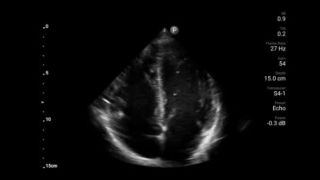

Early detection can help keep conditions from becoming critical

Congestive heart failure is a growing issue today. Discovering it earlier with in-office ultrasound can greatly improve survival rates.

Cardiac tamponade masquerades as abdominal pain

Assessment of left ventricular function